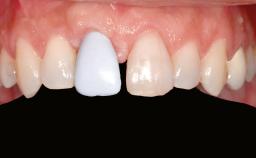

A woman in her mid-fifties was referred by a dental student for dental implant placement. Both posterior segments of the mandible had been edentulous for more than 4 years, the only residual tooth being the right lower first premolar. The patient had used a removable partial denture but was not entirely satisfied with its function. The clinical examination revealed a sharp edentulous ridge in both posterior segments of the mandible, and the patient was told that it would not be possible to insert implants into this thin edentulous ridge without significant augmentation of the alveolar ridge. Her medical history revealed no significant findings and no underlying disease that might have complicated surgical procedures. During the presurgical examination, the patient reported that she was a little apprehensive about bone grafting. After being informed about the surgical procedures and potential postoperative complications, she accepted the proposed surgical plan of bone grafting and subsequent placement of implants.

Bone Volume Deficient horizontally, requiring prior grafting